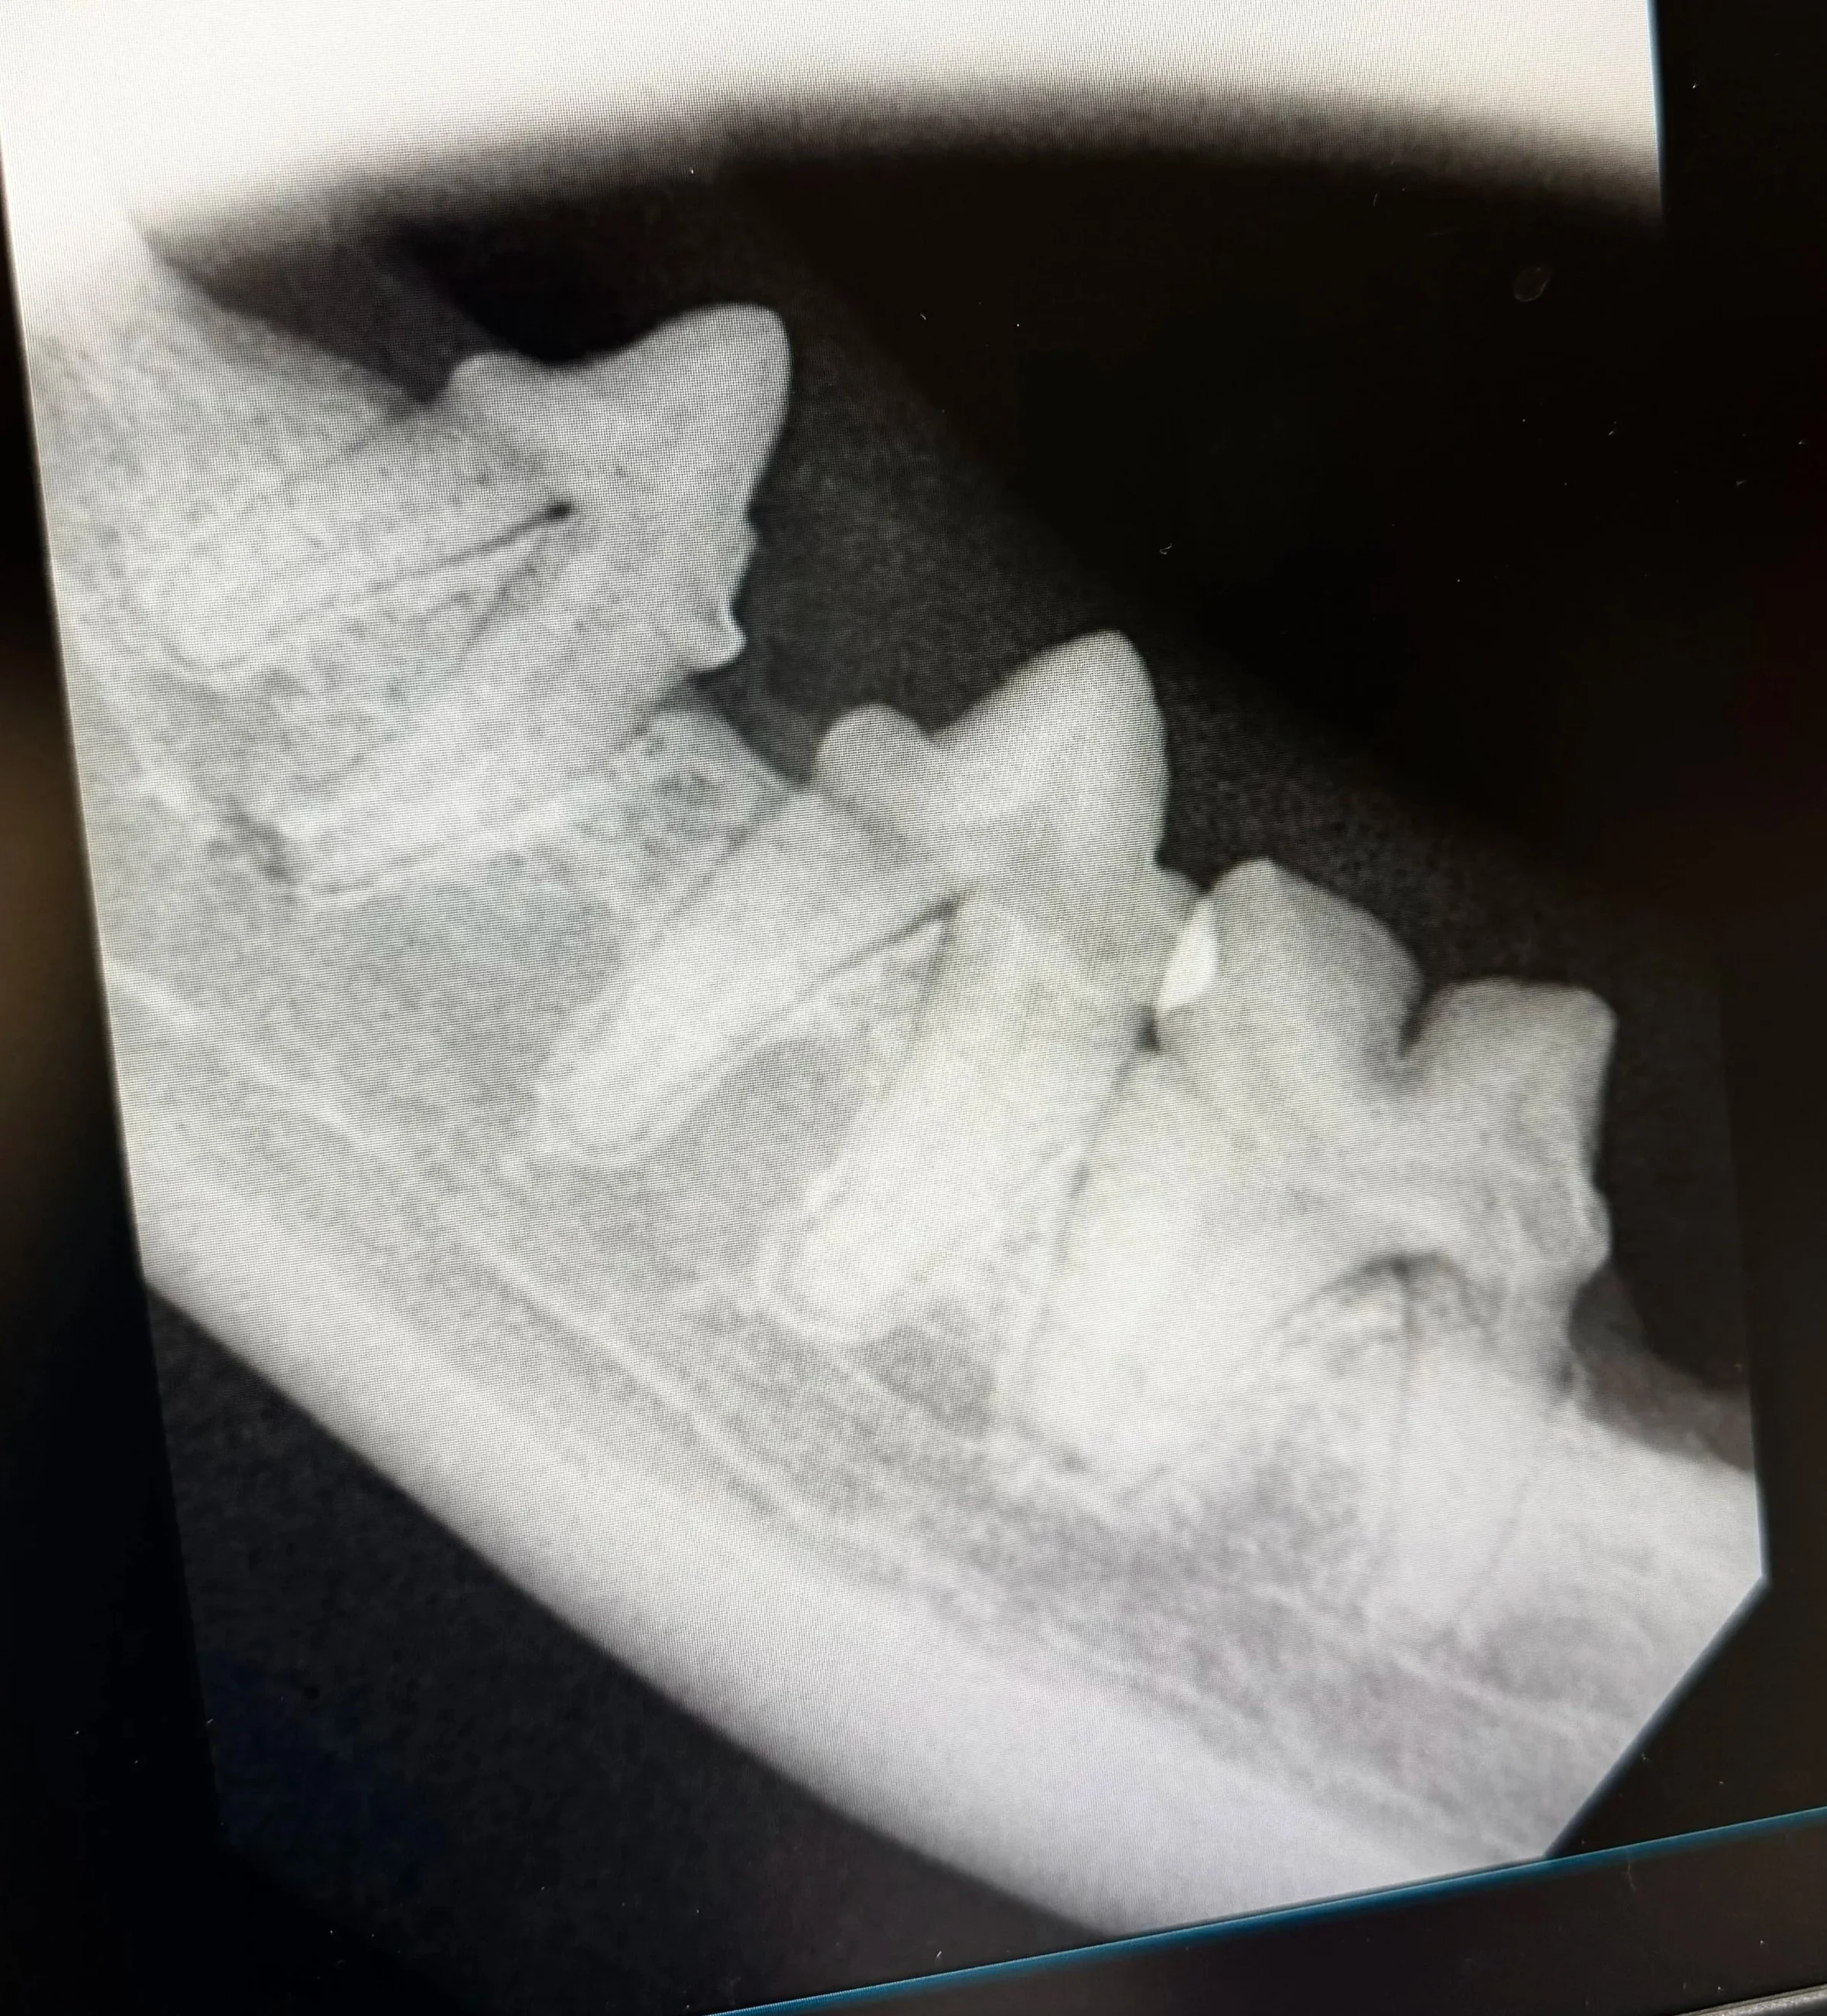

Digital Dental X-Rays

Advanced imaging that allows us to evaluate tooth roots and bone beneath the gums—where most dental disease in cats occurs.